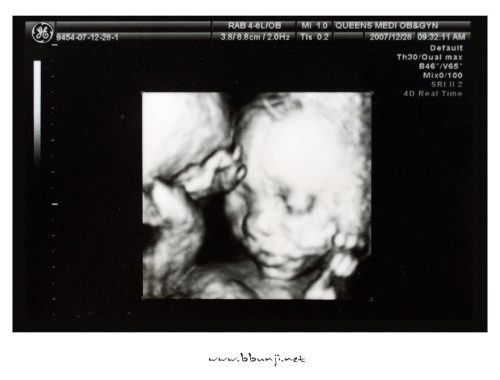

사랑이… 20주 째.. *^^*

2007.12.28 짜잔~~ 드디어 우리 사랑이 얼굴 공개… 병원에서 정밀초음파를 했는데 우리 사랑이 얼굴이 잡혔네요. 손으로 얼굴을 가리고 있어서 지은이가 물 두컵 마시고 계단을 7층까지 오르락 내리락 두번이나 했습니다.ㅋㅋ 이쁘게 생겼죠..^^ 아직 살이 덜 붙어서 좀 마른…